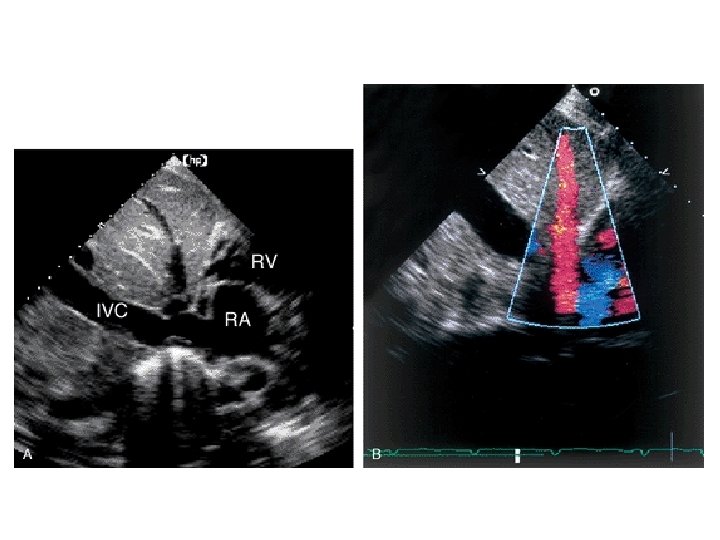

SUBCOSTAL LONG AXIS

SUBCOSTAL 4 CHAMBER VIEW